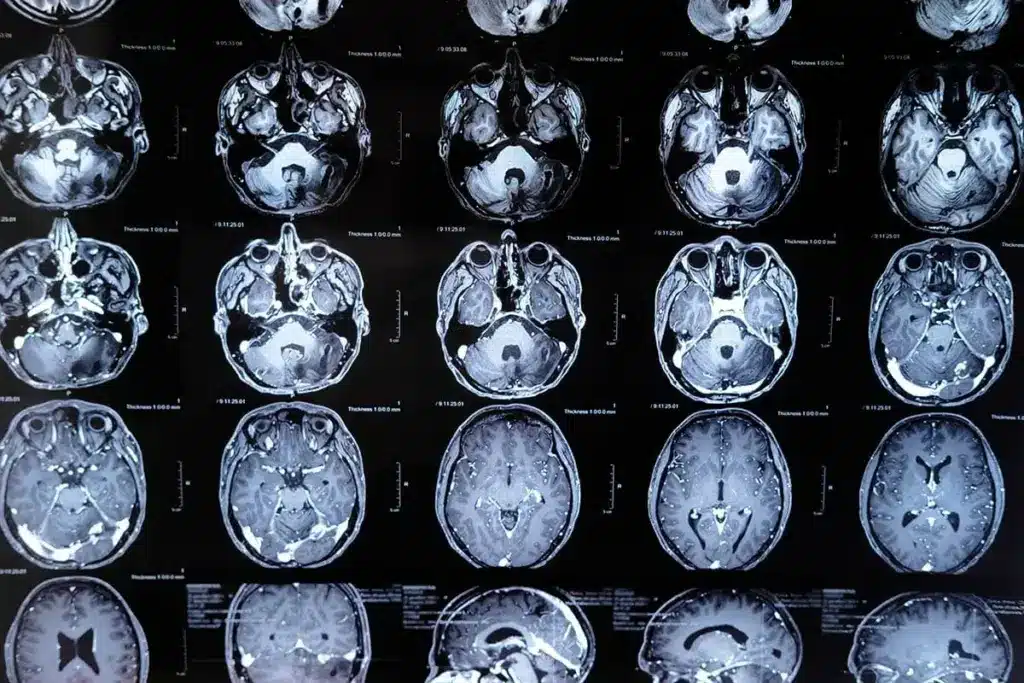

Brain tumors can start in any part of the brain or skull. This includes the protective lining and the underside of the brain (skull base). They can also form in the brainstem, sinuses, and nasal cavity. The brain‘s complex structure makes it possible for tumors to develop in different areas.

The brain is made up of several parts. These include the cerebrum, cerebellum, and brainstem. Each part can be a possible site for tumor growth. Knowing where brain tumors come from is key to diagnosing and treating them well.

Knowing the brain’s layout is key to finding where tumors might grow. The brain is a complex organ with different parts handling various tasks. Tumors can pop up in any area, messing with the brain’s functions.